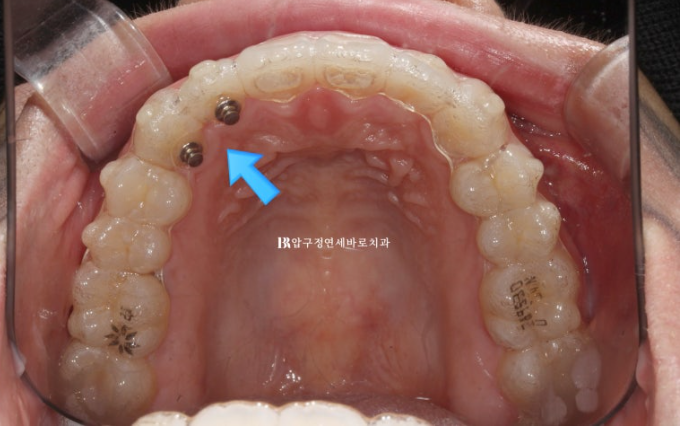

파란 화살표는 송곳니끼리 거꾸로 물리는 반대교합도 보입니다.

앞니가 삐뚤하고 아래 악궁 모양이 둥글지 않고 네모진 형태입니다.

파란 화살표는 고무줄을 거는 고리이고 앞니는 보이는 부위라서 투명한 고리에 치아를 붙였습니다.

23.11

위에는 입천장 보이지 않는 부위라 튼튼한 메탈 고리를 붙이고 고무줄을 걸기 시작합니다.